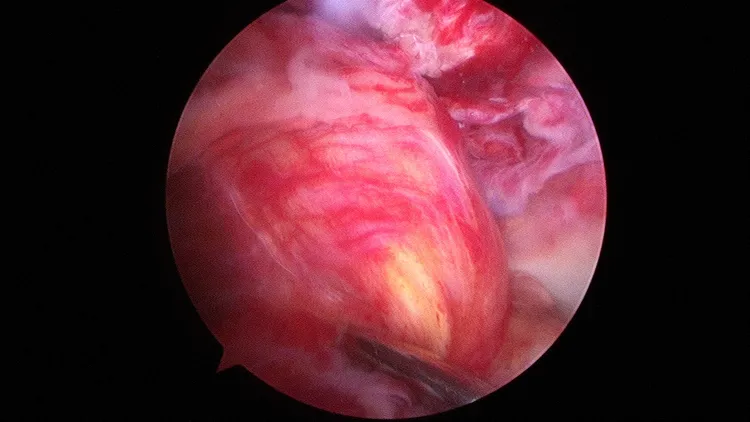

陳男膝關節鏡檢查前後十字韌帶都斷裂。大里仁愛醫唍提供